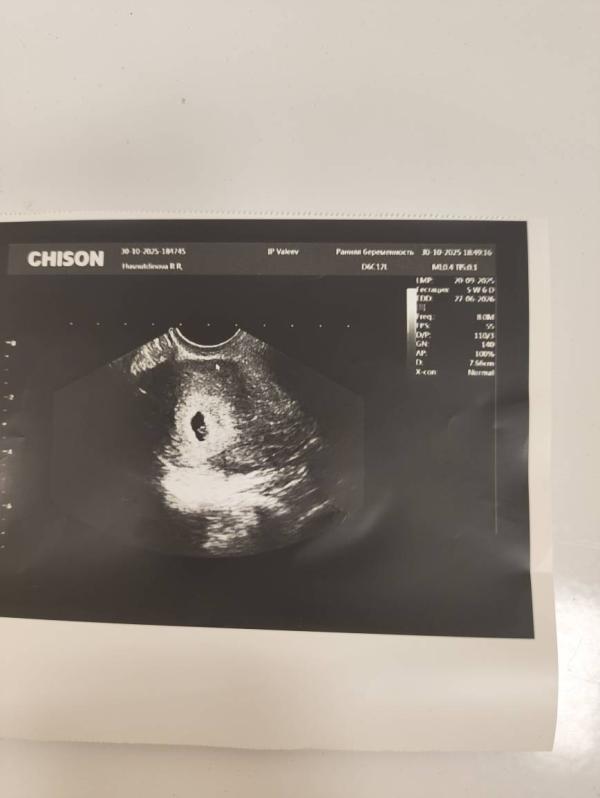

Делала узи 30.10. вдпя 10 мм

Сегодня сделали узи вдпя 12мм

Но говоит не видно эмбриона

Такое может быть? Если нет эмбриона но растет